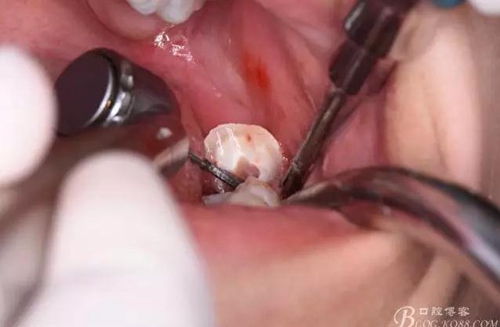

圖10.用丁字挺取出牙冠舌側(cè)部分

圖11.取出的38舌側(cè)部分

圖12.接著取出38的頰側(cè)部分牙冠